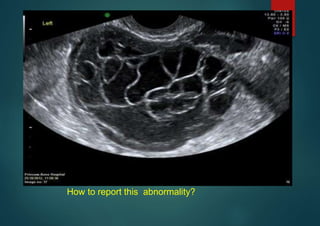

By the end of this presentation you will be able to report this!

How to report this abnormality?